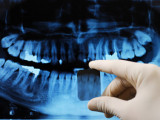

• panoramique ou orthopantomogramme, cette radiographie permet de visualiser la totalité de la bouche, d'une articulation à l'autre.